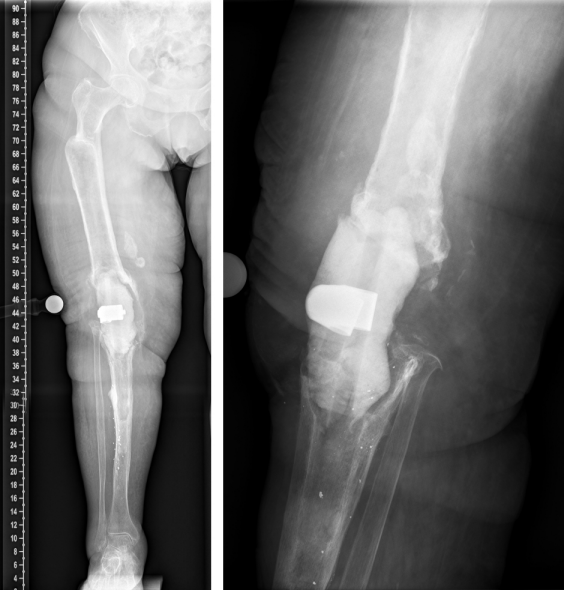

The duration of the surgical intervention was four hours and eight minutes. The patient was then mobilized with full weight bearing supervised by physiotherapists at ward level, which she tolerated well. The pain was significantly relieved during the hospital stay. The postoperative radiographs showed correct implant position and a satisfactory surgical result (Figure 9 [Fig. 9]). Microbiological and histological samples obtained intraoperatively showed no evidence of infection. Yet, the patient presented postoperatively with complete loss of active dorsiflexion of the ipsilateral foot. Neurological consultation and investigation confirmed the diagnosis of peroneal lesion. The patient was supplied by orthopedic shoes and orthesis. Further, electrotherapy was carried out.

Figure 9: The postoperative radiographs showed correct implant position and a satisfactory surgical result.